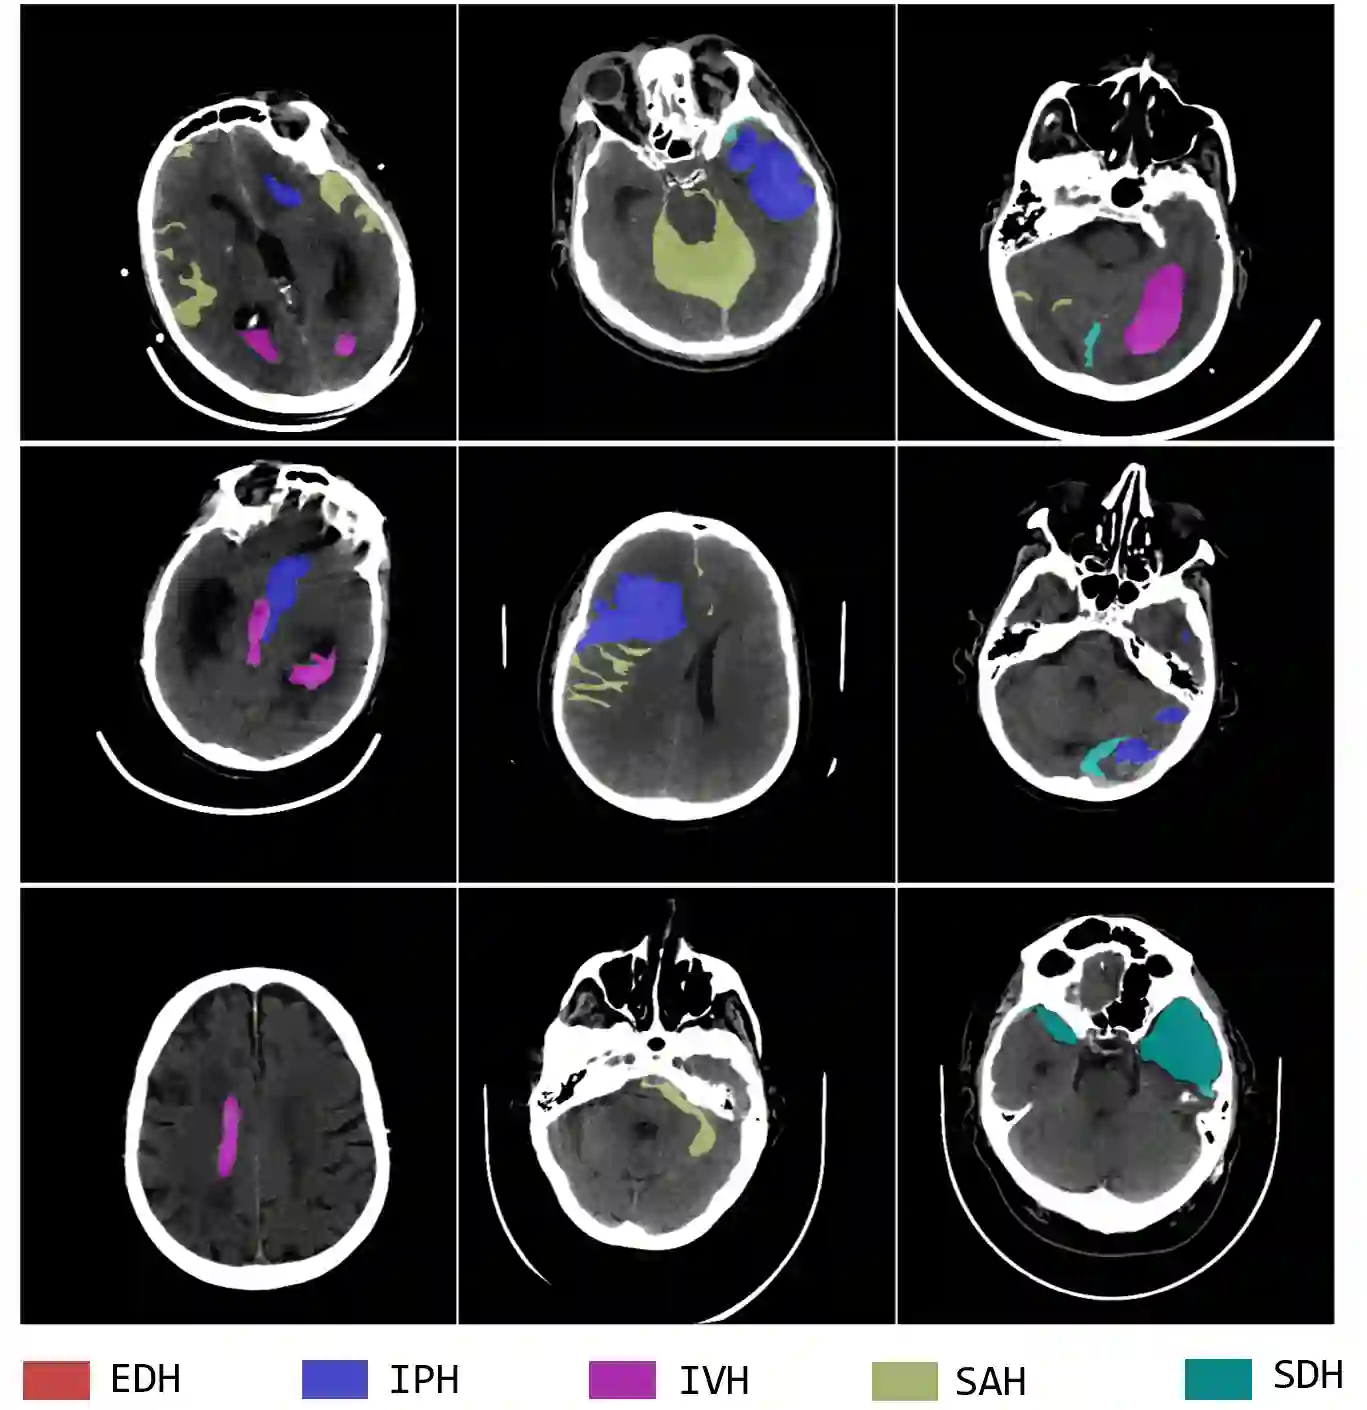

Intracranial hemorrhage (ICH) is a pathological condition characterized by bleeding inside the skull or brain, which can be attributed to various factors. Identifying, localizing and quantifying ICH has important clinical implications, in a bleed-dependent manner. While deep learning techniques are widely used in medical image segmentation and have been applied to the ICH segmentation task, existing public ICH datasets do not support the multi-class segmentation problem. To address this, we develop the Brain Hemorrhage Segmentation Dataset (BHSD), which provides a 3D multi-class ICH dataset containing 192 volumes with pixel-level annotations and 2200 volumes with slice-level annotations across five categories of ICH. To demonstrate the utility of the dataset, we formulate a series of supervised and semi-supervised ICH segmentation tasks. We provide experimental results with state-of-the-art models as reference benchmarks for further model developments and evaluations on this dataset.